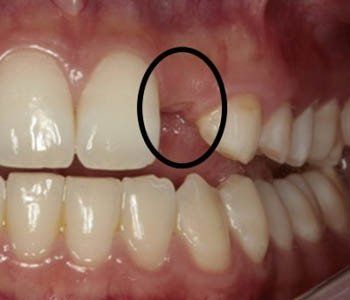

Diastema or Spacing

There is spaces or gaps between the teeth.